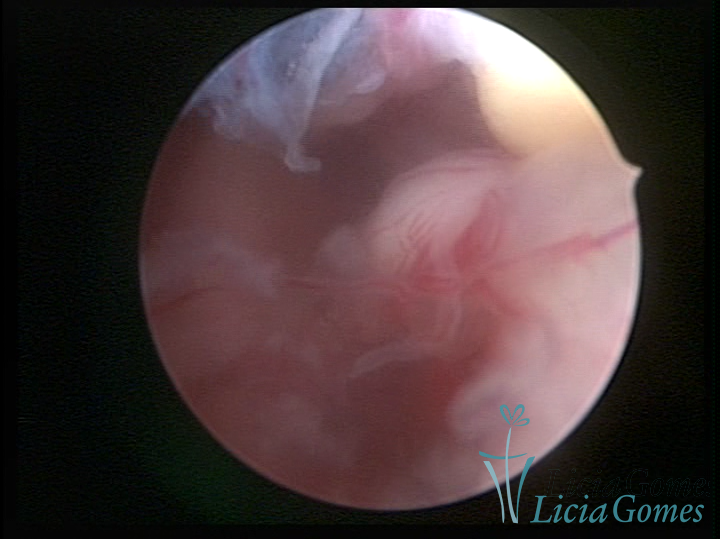

Este pode apresentar uma gama variável de aspectos macroscópicos, com aspecto pseudopolipoide; lembrando tecido cerebroide ou com reação deciduoide;a vascularização superficial é mais evidente e com vasos em formatos de saca-rolha ou espirais visualizando também a vascularização com atípias, com aumento do calibre dos vasos superficiais, pode ser encontrado também tecido em necrose, poderá haver um pequenos dendritos (papilomatoso).